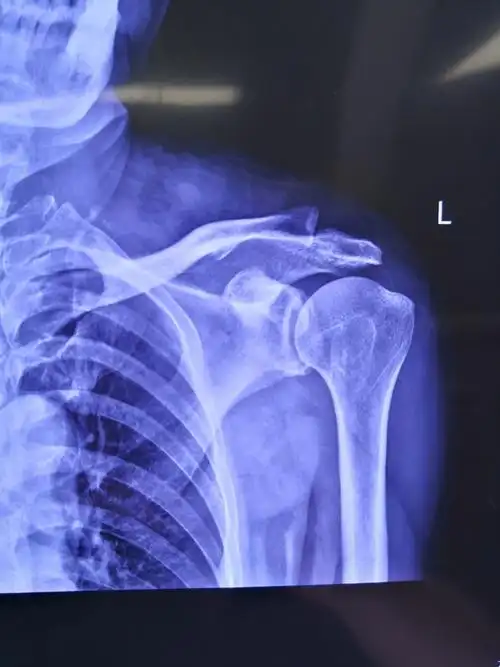

术前左肩关节正位片提示:左肱骨大结节处骨赘形成(肩峰撞击引起)